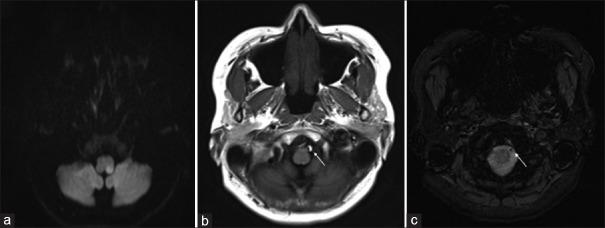

In the present vignette, we describe a lateral medullary infarction developed immediately after strenuous straining owing to constipation in a 42-year-old female. There was a dissection in left vertebral artery V4 segment. Computed tomography (CT) angiography revealed beaded appearance of cervical V2 and V3 segments of bilateral vertebral arteries. A follow-up CT angiogram performed about 3 months later showed resolution of vasoconstriction and normalization of vertebral arteries. Reversible cerebral vasoconstriction syndrome (RCVS) is usually known as an intracranial pathologic condition. Extracranial RCVS is very rare. Therefore, the diagnosis of RCVS could be challenging when its location is extracranial, particularly when comingling vertebral artery dissection (VAD) is present because of their similar vascular luminal morphology. Physician should be vigilant about the possibility of a concomitant presence of RCVS and VAD, even in extracranial vessels.

在本病例中,我们描述了一名42岁女性因便秘用力排便后立即发生的延髓外侧梗死。左椎动脉V4段存在夹层。计算机断层扫描(CT)血管造影显示双侧椎动脉颈段V2和V3段呈串珠样改变。约3个月后进行的随访CT血管造影显示血管收缩消失,椎动脉恢复正常。可逆性脑血管收缩综合征(RCVS)通常被认为是一种颅内病理状态。颅外RCVS非常罕见。因此,当RCVS位于颅外时,尤其是合并椎动脉夹层(VAD)时,由于它们相似的血管腔形态,RCVS的诊断可能具有挑战性。即使在颅外血管中,医生也应警惕RCVS和VAD同时存在的可能性。